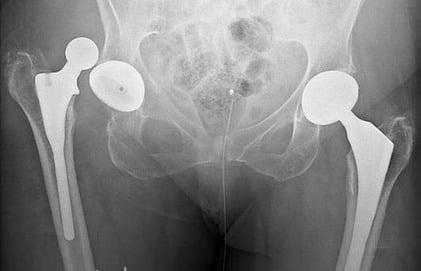

Изображение положения эндопротеза в теле человека.

Дислокация бедренного компонента на рентгене.